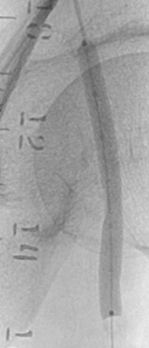

术前

LiqMagic P18放电前